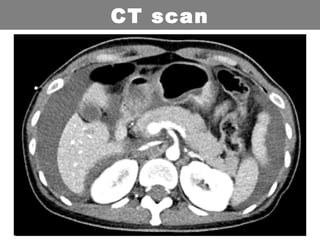

CT scan

For haemodynamically stable patients

• Definitive imaging with multidetector CT Abdo/pelvis

is performed in haemodynamically stable when an

emergency laparotomy is not indicated and one of

the following is present:

• Trauma patients with abdominal tenderness

• Trauma patients with altered sensorium

• Distracting injuries or injuries to adjacent structures

CT abdomen (97% sensitive for peritoneal violation) is

usually performed to look for evidence of peritoneal

penetration and intraperitoneal injury:

• free air

• free fluid

• bowel wall thickening

• wound tracts adjacent to a hollow viscussolid organ

injury